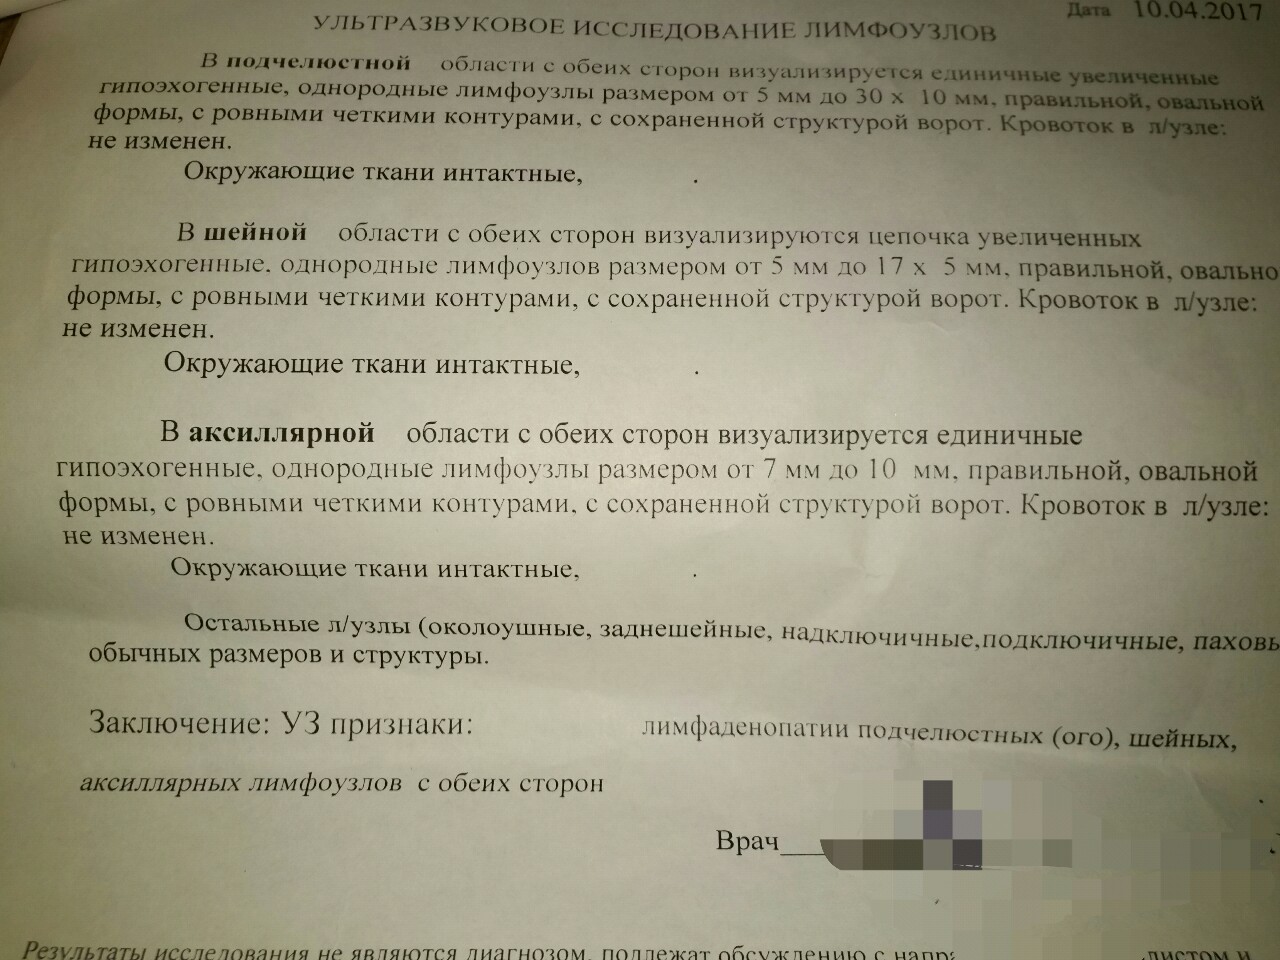

УЗИ лимфоузлов при лимфоме Ходжкина

Раздел: Образы вокруг